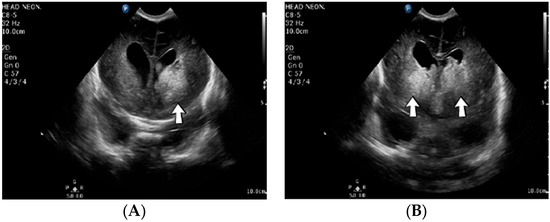

4.36. Case No. 36—Postnatal Intracardiac Thrombosis

A 7-week-old male infant (36 weeks, 2.50 kg), the first twin from a twin pregnancy, presented with a complex congenital cardiac malformation for an elective surgical procedure (Blalock–Taussig shunt). Heparin infusion for the shunt was started immediately after the intervention and anticoagulation was continued with enoxaparin due to good clinical condition. Then, 18 days after the procedure, a routine cardiovascular ultrasound revealed a thrombus in the left ventricle (Figure 16). The laboratory studies showed leukocytosis, highly elevated c-reactive protein, and modified coagulation tests (due to anticoagulant treatment). Continuous heparin infusion was reinitiated, but multiple intracardiac thrombi were detected during the following days. Treatment with alteplase was also started, but the patient’s condition continued deteriorating, leading to a negative outcome due to cardiac failure.

Figure 16.

Intracardiac thrombosis identified on cardiac ultrasound: left atrium and ventricle (A), left ventricle (B), apex (C).

Genetic testing confirmed inherited thrombophilia, with positive PAI-1 4G/5G promoter, MTHFR A1298C homozygous gene mutations, and Antithrombin and Protein C deficiencies. There was no known family history of thrombophilia. The mother had a previous therapeutic abortion due to a prenatal diagnosis of a complex congenital cardiac malformation.